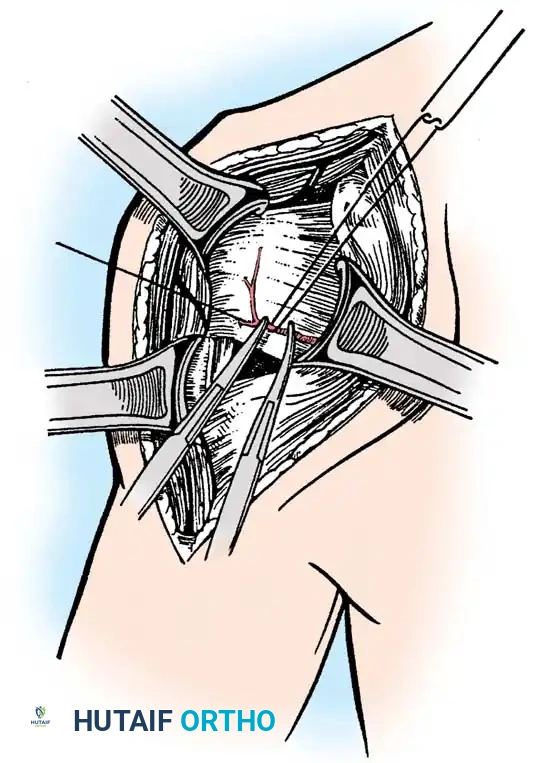

Surgical Technique: Total Elbow Arthroplasty

1. Positioning and Approach

The patient is placed in the lateral decubitus position with the arm draped over a bolster. A universal posterior approach is utilized.

- Ulnar Nerve Management: The ulnar nerve must be identified, mobilized, and protected throughout the procedure. Routine anterior transposition is performed at the conclusion of the case.

- Triceps Management: Several options exist, including a triceps-reflecting approach (Bryan-Morrey), a triceps-splitting approach, or a triceps-sparing approach. The Bryan-Morrey approach involves reflecting the triceps from medial to lateral in continuity with the anconeus and forearm fascia.

2. Joint Preparation

The tip of the olecranon is excised to facilitate access to the medullary canal. The distal humerus is prepared by resecting the trochlea and capitellum, preserving the epicondyles if possible to maintain collateral ligament attachments (though less critical in linked designs).

4. Closure

The triceps mechanism is meticulously repaired using heavy non-absorbable sutures through drill holes in the proximal ulna. The ulnar nerve is secured in a subcutaneous anterior transposed position, ensuring no fascial bands compress it.